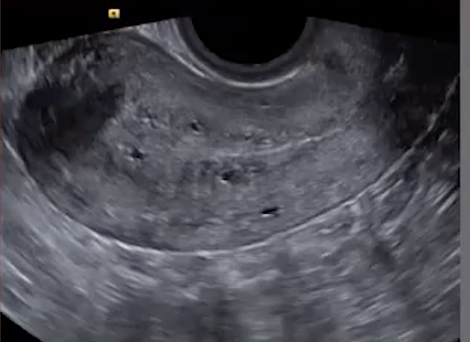

• Findings

• Ectopic endometrial glands

• Echogenic nodules/striations or small cysts (US to R)

• Small cysts at the endometrial-myometrial junction are most sensitive & specific finding for adenomyosis (green arrow)

• Venetian blinds appearance

• Alternating stripes of increased and decreased echogenicity - looks like light coming through the blinds to me (bottom image)

• Need to make sure the lines don’t go back to the arcuate arteries within the uterus itself, that’s just artifact

• Ill defined endometrial-myometrial junction